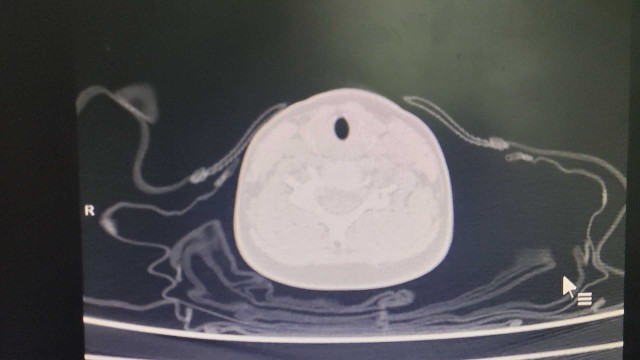

月叔打怪兽急诊科医师

昨天值班遇到的一例晕厥病例,差点漏诊,而最终的解法,始于最简单而质朴的查体。国庆中秋双节的最后一天,8号的早上8点,抢救室床旁晨交班,病人依旧是多而重,交到6床,一个刚入室不久的病人,准备去做CT,夜班医师汇报病史:69岁男性,本次因“头晕伴一过性晕厥1小时”为主诉入抢,1小时前于高铁站因即将赶不上高铁走路快时突发头晕,伴一过性晕厥,约3-4分钟后清醒,清醒后诉今晨未吃早餐,已服用降压药物,仍有头晕头痛、四肢乏力等不适,无胸闷胸痛,无畏寒发热,无咳嗽咳痰,无恶心呕吐,无肢体麻木,无视物模糊等不适,路人拨打120送至我院急诊就诊。既往高血压,长期服用氨氯地平+福辛普利,血压控制一般;糖尿病,长期